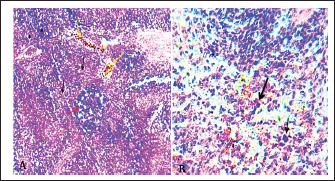

The microscopic examination of the liver and spleen sections revealed moderate to severe pathologic changes compared with the normal histological view of the sections from the control group. The histopathological figure of the infected liver showed hepatitis with multiple necrosis of hepatocytes and marked aggregation of the mononuclear leukocytes, periportal aggregation of leukocytes, with dilation of portal veins (Fig. 5). Histopathology of infected liver reveals chlamydial inclusion bodies (IB) within the cytoplasm of macrophages, as shown in Figures 68.

Fig. 5. A). Section of liver (Control) shows a normal central vein (V), a normal hepatic cords (h). H&E.100x. B). Section of liver (infected) shows hepatitis with multiple necroses (black arrows), periportal aggregation of leukocytes with dilation of portal veins (red arrow). H&E.100x.

Fig. 6. Section of infected liver with C. psittaci shows marked aggregation of the mononuclear leukocytes with chlamydial reticulate inclusion bodies (IB) within the cytoplasm of macrophages (Arrow), H&E stain, 400x.

Fig. 7. A). Section of chlamydial-infected liver shows chlamydial reticulate inclusion bodies (IB) within the cytoplasm of hepatocytes (Arrow), H&E stain, 400x. B). Section of infected liver shows inclusion bodies (IB) stained purple within the cytoplasm of macrophages (Arrows) with periportal aggregation of leukocytes and dilation of portal veins, Giemsa stain, 400x.

Fig. 8. Section of liver (infected) shows chlamydial inclusion bodies (IB) within the cytoplasm of macrophages (Arrows), 400x, A). Giemsa stain, B). Gimenez stain.